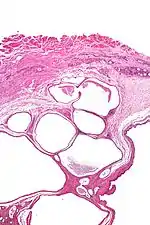

| Micrograph of a cystic tumour of the atrioventricular nodal region. H&E stain. | |

Cystic tumours of the atrioventricular nodal region, true to their name, have cystic spaces, which are lined by a single layer of histomorphologically benign epithelial cells. The appearance is similar to that of lymphangioma and this is a name that has been used for this tumour.[1]